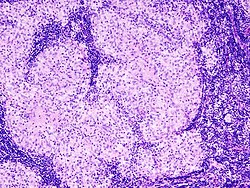

Kora ima vanjsku zonu (sekundarni limfni čvorići i difuzno limfno tkivo među njima sadrže limfocite B) i unutrašnju (parakortikalnu) zonu (parakorteks, difuzno limfno tkivo koje sadrži limfocite T, zona ovisna o timusu). Moždina (meduča) se neposredno nastavlja na koru u obliku razgranjenih i međusobno povezanih moždinskih (medularnih) tračaka (difuzno limfno tkivo, sadrži limfocite B).

Limfni sinusi su široki, nepravilni prostori (usporen protok limfe povoljan za izmjenu limfocita i fagocitnu aktivnost), nepotpuno obloženi spljoštenim retikulskim (litoralnim) stanicama. Njihov lumen je premošćen retikulskim stanicama (sposobnost fagocitoze) retikulskim vlaknima i makrofagima. Kroz čahuru ulaze u limfni čvor aferentne limfne žile i dovode limfu koja sukcesivno prolazi kroz limfne sinuse smještene između čahure i kore (periferni supkapsularni ili marginalni sinusi), između kore i trabekula (kortikalni, peritrabekularni ili intermedijarni sinusi) i između moždinskih trčaka (moždinski ili medularni sinusi).